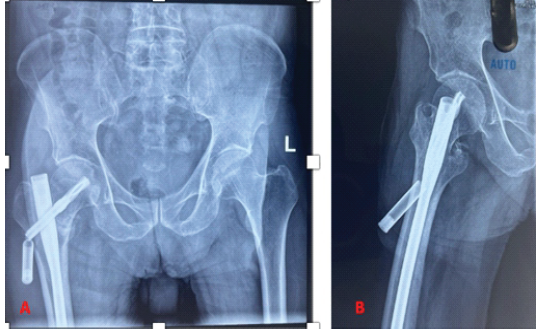

The perioperative period was uneventful, and the patient was started on partial weight-bearing walking with the aid of a walker after assessment of the reduction on the post-operative radiograph. He underwent suture removal on day 14 post-operative, and he had an uneventful recovery at the 6-week follow-up. However, he presented 2 weeks later with pain in the proximal thigh and a palpable hard mass. The patient did not report any history of accidental falls, was afebrile, and the local site was unremarkable. The inflammatory indicators were within the normal range (erythrocyte sedimentation rate 18 mm/h, C-reactive protein 2 mg/dL). Our clinical diagnosis was screw pull-out, varus collapse, and implant failure; however, imaging revealed that the distal half of the helical blade had uncoupled from the blade and was impinging on the skin (Fig. 4 and 5).

Figure 4: Anterior posterior (a) and lateral radiograph (b) showing uncoupling of helical blade.

The patient remained asymptomatic till the 12-month follow-up, and a computed tomography was obtained, which revealed a fibrous non-union. However, the patient was asymptomatic and did not have any limp or abductor lurch, and the Harris Hip Score was 84. The head was viable, and options were explained to the patient, who opted for conservative management (Fig. 7).

Figure 7: X-ray at follow-up of 18 months.